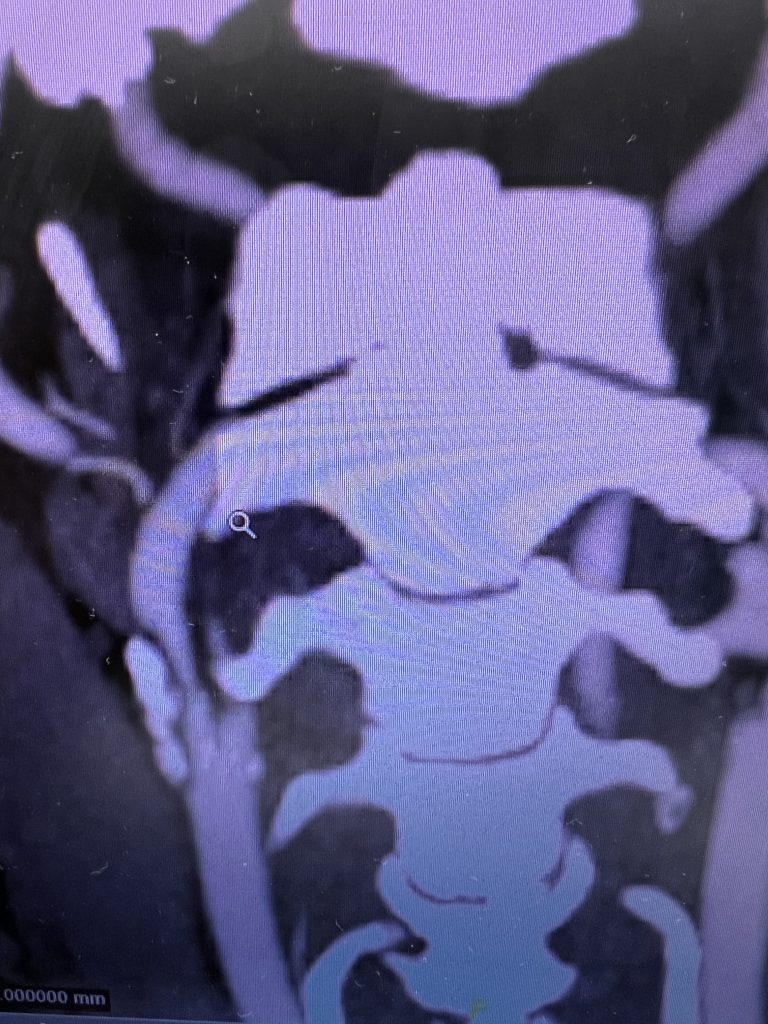

He was studied with noninvasive imaging most significantly, which was a CTA that confirmed a high-grade carotid stenosis from a calcified atherosclerotic plaque. This is seen in Figure 3 which is a coronal CTA. The patient was evaluated for carotid revascularization, and given the high-grade critical stenosis detected on the CTA and the carotid duplex, he was a good candidate, given the high-stroke risk of the lesion if left untreated.

Fig. 3 – Pre-operative CTA image confirms high-grade carotid stenosis from a calcified atherosclerotic plaque.